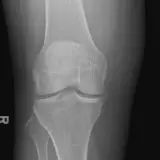

Over 2,100 interactive radiology cases, curated by radiologists for your level of training. Scroll, window, and view cases full screen — just like on PACS. Click linked findings in each writeup to jump straight to them on the image. Cases include sample reports, a focused discussion section, original illustrations, and videos.

PACSで期待されるツールを完備した完全インタラクティブな症例 — スクロール、ウィンドウ調整、ズーム、パン、計測、ROI、フルスクリーンモード。

重要な所見を症例画像上に直接ハイライトする豊富なアノテーション。症例解説内のリンクされた所見をクリックすると、スキャン上の正確な位置へジャンプできます。

職場のPACSステーションと同じようにスクロール、パン、ウィンドウ調整、ズームが可能